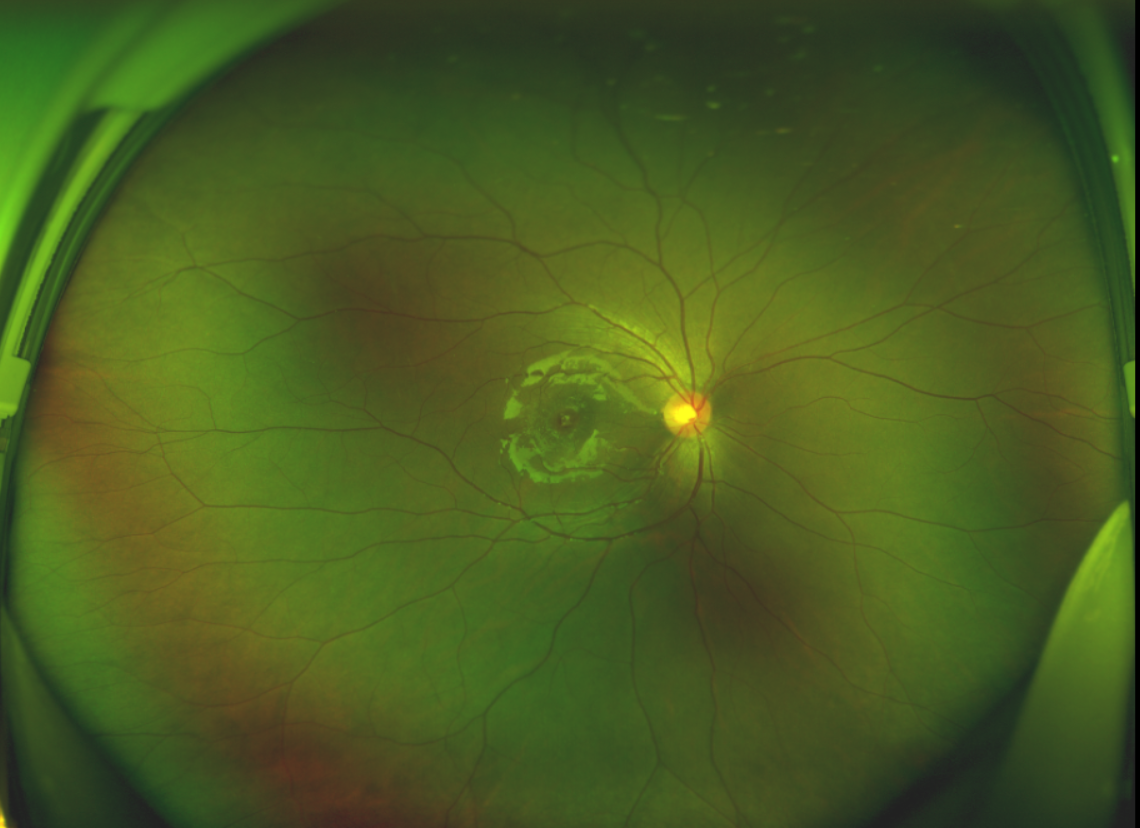

半年前的一次意外,誠誠(化名)右眼不慎受傷導(dǎo)致黃斑裂孔。從此,他的“視”界不再清晰,也不再有直線條……

黃斑位于視網(wǎng)膜正中心,是視覺最敏銳的區(qū)域,堪稱“眼底的心臟”,負(fù)責(zé)我們閱讀、駕駛、識(shí)別人臉等精細(xì)視覺。 當(dāng)黃斑區(qū)的神經(jīng)組織出現(xiàn)全層缺損,形成一個(gè)“孔洞”,即為黃斑裂孔,它會(huì)直接導(dǎo)致中心視力急劇下降、視物變形、視野中心出現(xiàn)暗區(qū)。

由于裂孔較小,當(dāng)?shù)蒯t(yī)院建議先觀察,看看裂孔是否能夠自愈??砂肽陼r(shí)間過去了,誠誠傷眼的裂孔不僅沒有愈合的跡象,反而越來越大,這讓家長的心揪得更緊了。

經(jīng)過詳細(xì)的檢查和評(píng)估,王曉波主任決定采用“內(nèi)界膜翻轉(zhuǎn)覆蓋聯(lián)合粘彈劑固定術(shù)”為誠誠進(jìn)行治療。

除此之外,利用自體組織覆蓋為黃斑裂孔提供了理想的愈合環(huán)境,裂孔閉合速度顯著快于傳統(tǒng)方法。誠誠接受手術(shù)24小時(shí)后,檢查可見內(nèi)界膜瓣位置良好;術(shù)后1個(gè)月,黃斑裂孔已經(jīng)閉合,視力恢復(fù)到0.5;術(shù)后兩個(gè)月,視力進(jìn)一步提升到0.7。